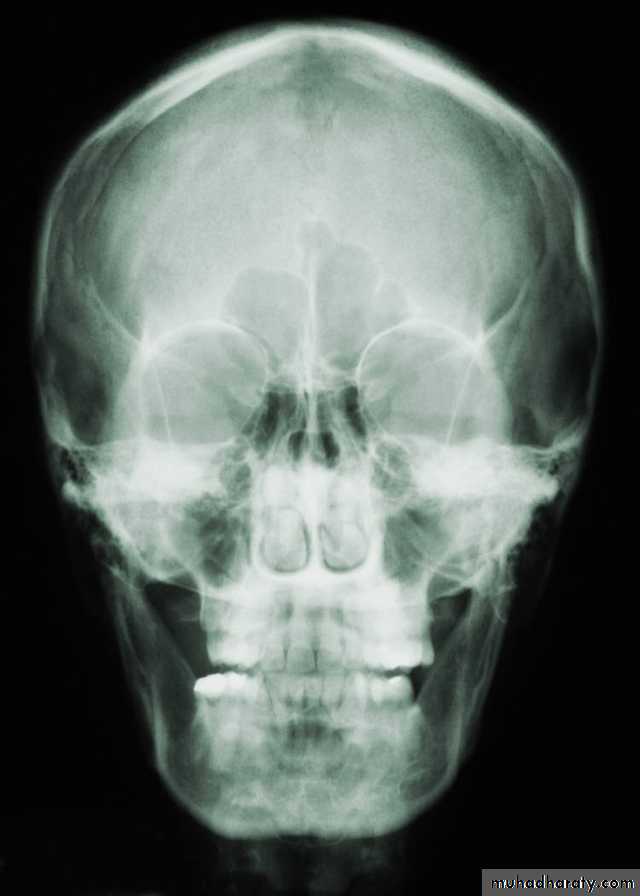

• A-Plain film: which have limited role in the radiological evaluation of facial trauma. Include:

• -Skull film(lateral and posteroanterior view).

Skull film

Lateral viewP-A view